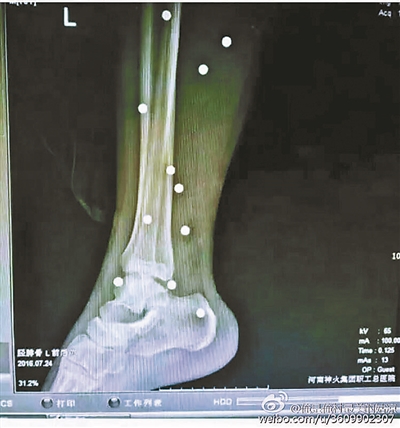

傷者體內(nèi)取出的鋼珠

爆炸導(dǎo)致鋼珠遍布傷者身體各處

黃明的伯伯對(duì)北青報(bào)記者表示,由于黃明直接踩到了爆炸物,所以傷情最為嚴(yán)重,“他的腿被炸斷,身體內(nèi)被炸進(jìn)了40多顆鋼珠。手術(shù)后已經(jīng)從體內(nèi)取出29顆鋼珠,還有十多顆鋼珠沒有取出來?!备鶕?jù)黃明的入院記錄,他全身有多處爆炸傷,且全身多處異物存留。